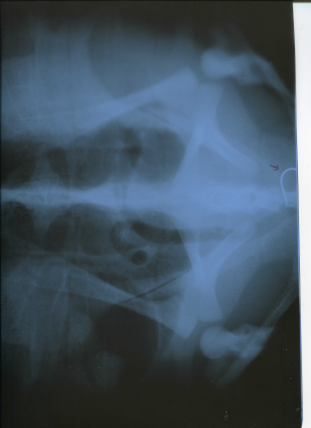

海生館表示,本月6日收容的綠蠵龜,經獸醫師初步觀察,外觀沒有明顯外傷,但略顯虛弱,經X光檢查,在消化道內發現魚鉤,目前正在海生館收容中心觀察中。

此外,4月份收容一隻來自台東的綠蠵龜,是由海巡署東部地區巡防局81岸巡大隊,通報海生館及台東縣政府。海巡人員表示,該海龜被發現時,嘴邊可看到魚線。經台東縣政府人員將海龜送去進行X光檢查,將結果轉知海生館獸醫師,獸醫師判定確實有魚鉤卡在食道,須立即取出。